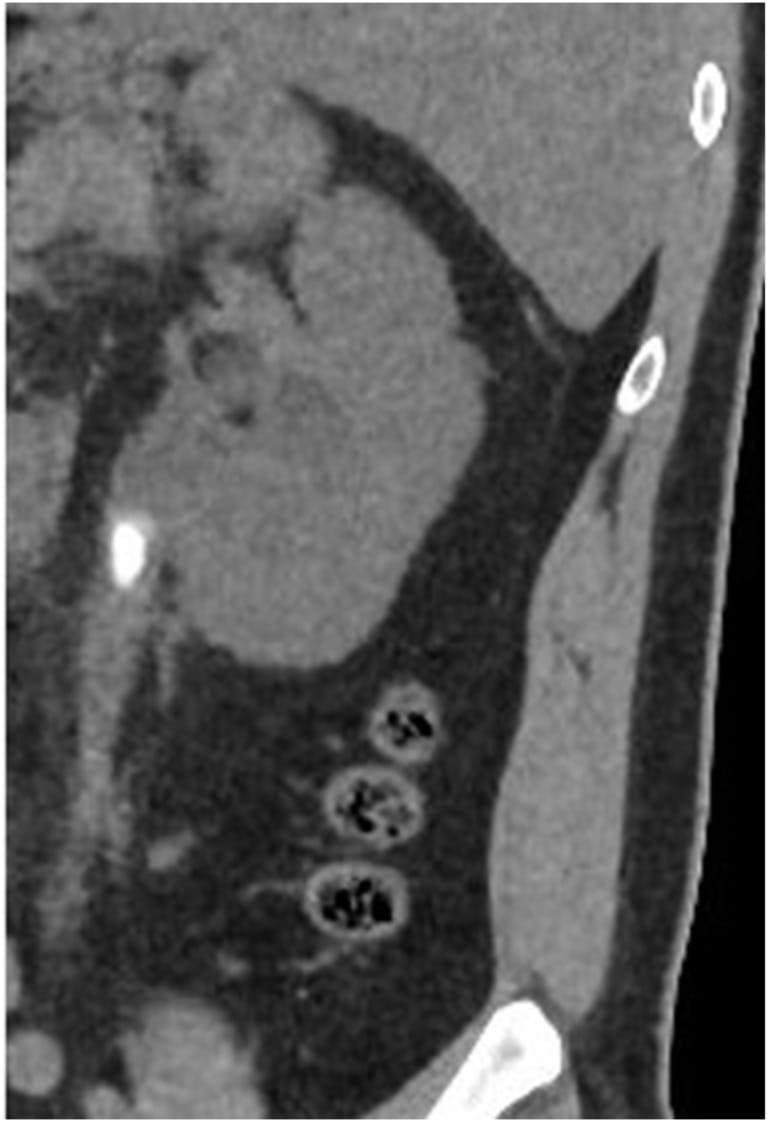

6 Tage nach der Operation entwickelte der Patient weitere Schmerzen im Lendenbereich und Fieber. Die CT-Untersuchung zeigte eine schwere linksseitige Hydronephrose, und der Stent war zusammen mit einem festsitzenden Stein in den mittleren Teil des Harnleiters gewandert (Abb. 2).

Abb. 2: CT-Aufnahme ohne Kontrastmittel, die einen eingeklemmten Stein im mittleren linken Ureter mit schwerer linksseitiger Hydronephrose zeigt.

© Aus: Al-Ibraheem H et al. Isolated renal aspergilloma. Urol Case Rep 2024;53:102688.